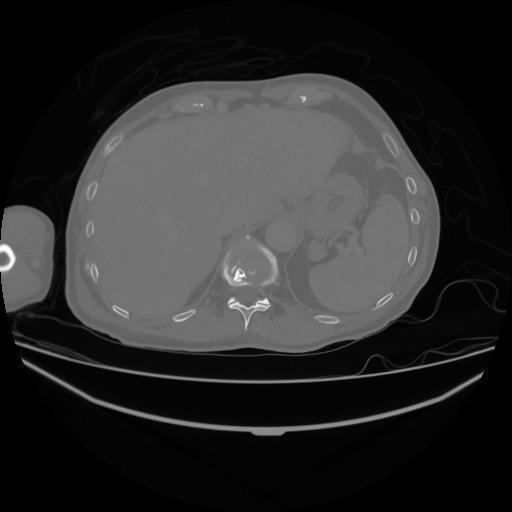

5 CUERPO,CE,Vol,1.0,CUERPO,,